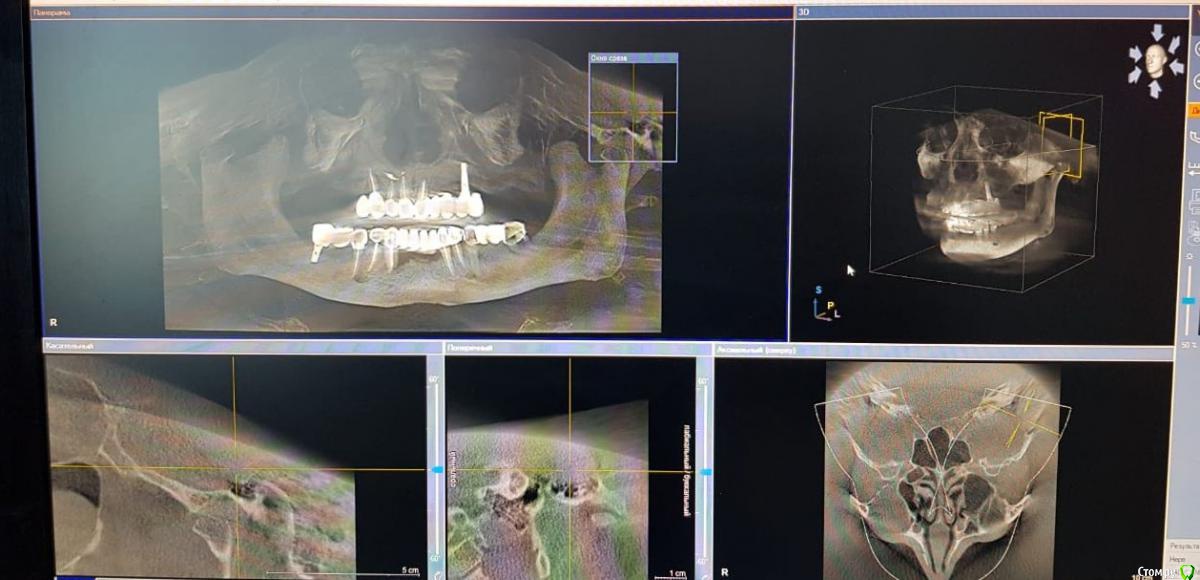

Sunshine Опубликовано 14 марта, 2019 Поделиться Опубликовано 14 марта, 2019 Уважаемые, врачи!Моему отцу 2,5 года назад установили импланты (в другом регионе), и сделали мост, "зацепившись" за живой зуб и имплант...Его ничего не беспокоило до недавнего времени. Теперь вся эта конструкция начала ходить ходуном ... приносит ему боль, естественно полноценно кушать не может.Обратившись в стоматологию по новому месту жительства, стоматологи сообщили, что так делать нельзя ни при каких обстоятельствах, и что надо все снимать, оставшиеся зубы удалять, ждать пока рассосется образовавшаяся киста в районе существующего импланта, и устанавливать новые импланты. Соответственно, вопрос. Так как отец в пенсионном возрасте, то крайне боится вообще остаться без зубов, для него это трагедия. Какие существуют варианты развития событий в нашей ситуации в "щадящем" режиме, но чтобы было все грамотно и четко сделано, дабы больше не возвращаться к вопросу зубов на верхнем ряду. p.s врач который устанавливал данную конструкцию сказал чтоб приезжали-он все поправит, но я его уже не отпускаю, потому что думаю это снова на пару лет...а дальше только хуже... Ссылка на комментарий

kramer Опубликовано 14 марта, 2019 Поделиться Опубликовано 14 марта, 2019 Если нужен несъемный протез, тогда надо удалять все зубы и прежний имплантат, одномоментно ставить 4-6-8 имплантатов (надо более детально изучать случай), временный несъмный протез в день операции или через несколько дней. Ссылка на комментарий

kramer Опубликовано 14 марта, 2019 Поделиться Опубликовано 14 марта, 2019 а что возможно сделать, не прибегая к удалению оставшихся зубов? Имеет ли смысл оставлять их? Какие последствия? Зубы верхней челюсти несостоятельны, сохранить нельзя Если на время удаления всей конструкции ставить съемный протез(это я так понимаю снимаются на ночь и в стаканчик? )), то это же только на то время пока не приживутся новые имплантаты? (примерно 3-6 месяцев) Временный протез несъемный, прикручивается в день операции или через несколько дней (при условии, что первичная стабильность имплантатов хорошая. Если нет, тогда как по сценарию, который вы написали) и что с кистой? Удаляется вместе с имплантатом Ссылка на комментарий